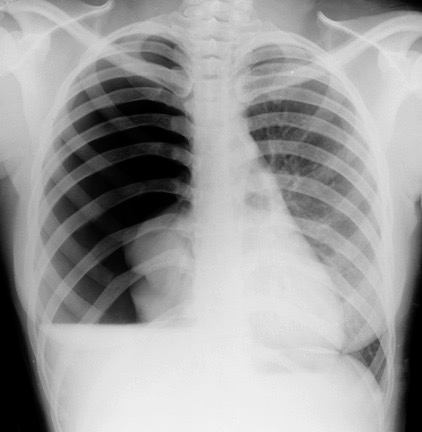

Tension pneumothorax

- Normal negative intrapleural pressure becomes positive.

- Depressing the ipsilateral hemidiaphragm.

- Pushing mediastinal structures to other side.

- Compressing contralateral lung.

- Tracheal deviation away from the affected side